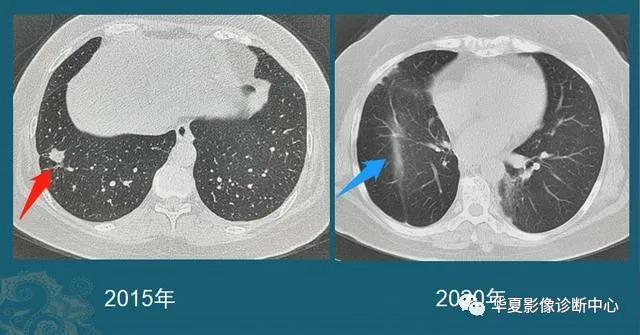

还有一种,随访过程中逐渐增大的肺结节,不论磨玻璃还是实性结节,都要重视!

绝大多数早期肺癌生长缓慢,对无法定性的肺结节,定期复查是个很实用的办法,可以避免过度医疗,也防止漏诊。

豪大夫每年都能发现很多从肺小结节长大的肺癌,挑出两个速度最快的分享一下:

这位病人2016年体检还是正常的,2017年查出一个3mm的肺结节,用了两年半时间,增长到>1cm,手术病理是肺腺癌。

注意:这几乎是最快的一类的,很少见!所以高危人群推荐每年胸部体检一次是有益的。

这是一位老年男性,有吸烟史,也是在两年多的时间内,肺结节从不足3mm长到1cm以上,后来病理确诊肺鳞癌。

中老年人定期胸部CT体检,可以及时发现这些生长较快的恶性肺结节,予以手术根治。